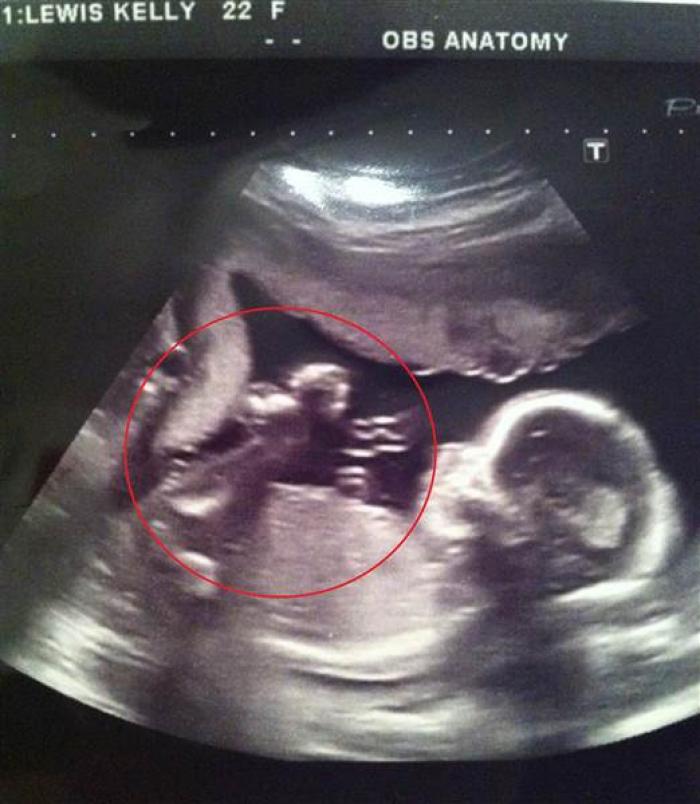

O femeie însărcinată a rămas mută de uimire la ecografie! Cine îi veghea copilul din pântece

Kelly Lewis, o femeie în vârstă de 26 de ani din Marea Britanie, a avut parte de o surpriză de proporţii după ce și-a făcut o ecografie 4D în timpul sarcinii.